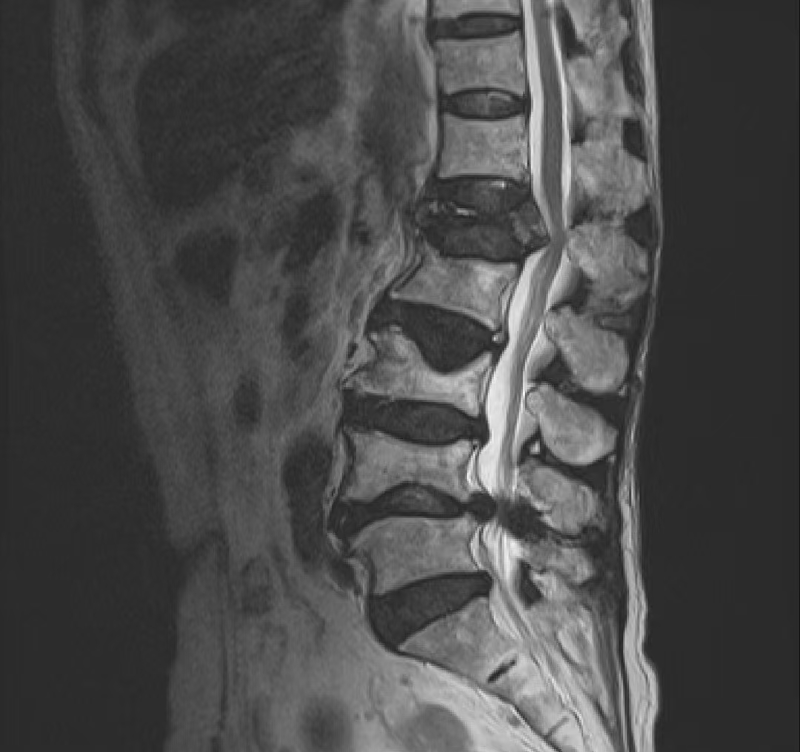

術前MRI:腰3/4、腰4/5椎間盤突出,伴椎管狹窄嚴重、神經根受壓、馬尾神經冗余。